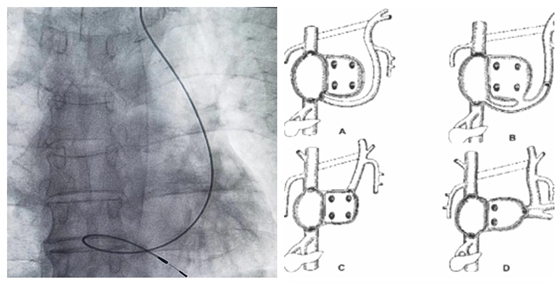

3月15日,湘雅常德医院心血管内科起搏电生理团队独立完成1例病态窦房结综合征合并永存左上腔静脉(PLSVC)患者永久起搏器植入术。 今年7...